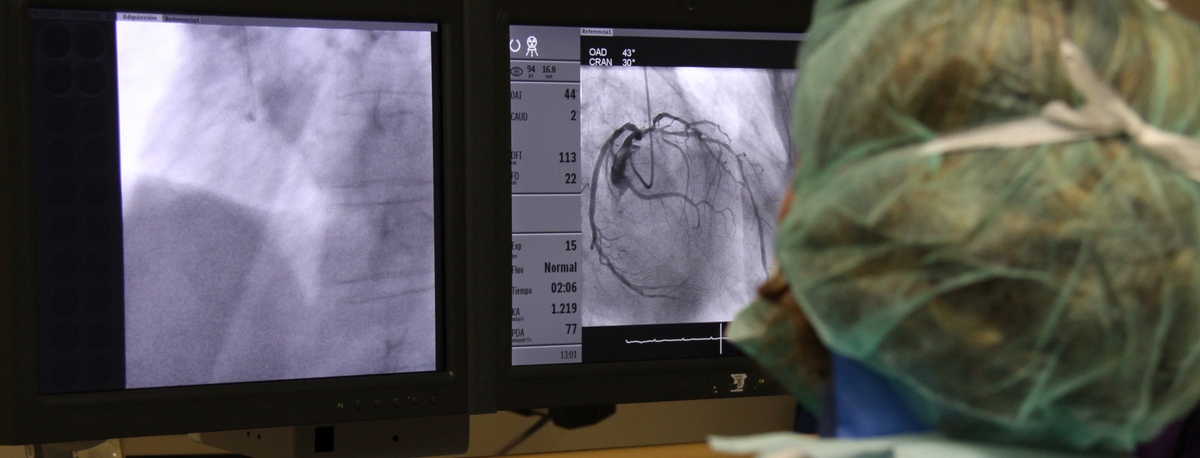

- Cardiac Diagnosis

Instituto del Corazón Teknon

Tratamientos y Especialidades

Angiología, Cirugía vascular y endovascular

Especialistas en cirugía arterial directa de extremidades, cirugía de varices, cirugía de aneurismas y cirugía carotídea

En el instituto contamos con especialistas en Angiología, Cirugía Vascular y Endovascular para el diagnóstico y seguimiento de las enfermedades del aparato circulatorio. La embolia cerebral y el tromboembolismo pulmonar son algunas de las principales causas de muerte debido a un problema vascular.

Nuestro equipo es especialista en técnicas mínimamente invasivas, utilizando técnicas endovasculares, sin cirugía, que permiten implantar prótesis vasculares para resolver dilataciones o aneurismas de las arterias. También ofrecemos todos los tratamientos de la patología venosa y arterial periférica, incluyendo las enfermedades de las arterias carótidas.